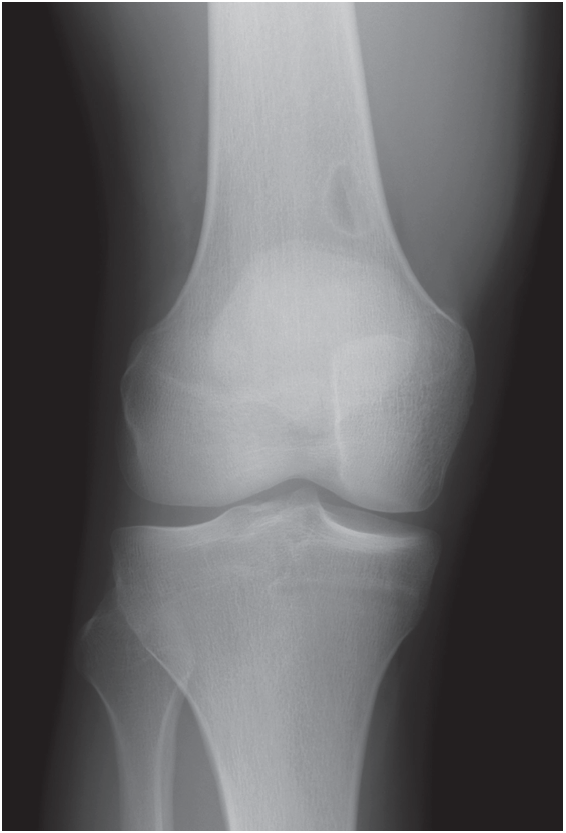

An 11-year-old girl presents with right knee pain following a low-impact injury while playing soccer and is unable to bear weight (Figure 6).

Figure 6 — An aneurysmal bone cyst on the right proximal tibia of an 11-year-old girl.

Aneurysmal bone cysts (ABCs) are benign, vascular tumors that grow rapidly and destroy bone. They typically are solitary lesions of adolescence that affect girls slightly more often than boys. They most commonly are located in the metaphyseal area of long bones but also are found in the posterior spinal elements and can be found in any bone in the body. They typically present with pain and pathologic fracture; neurologic deficit is possible if the spine is involved.

The typical radiographic appearance of an ABC is an aggressive, well-circumscribed, expansile, eccentric, lytic lesion. They are described as having a soap-bubble appearance. Plain radiographs may be diagnostic, but if there is any uncertainty or if the lesion is not in a long bone, axial imaging can clarify the diagnosis by demonstrating multiple fluid–fluid levels in the cystic spaces.1

Surgical treatment of ABCs usually is required and consists of curettage and bone grafting with or without internal stabilization, depending on the size and location of the lesion. A significant risk of recurrence exists in up to 20% these lesions after treatment.